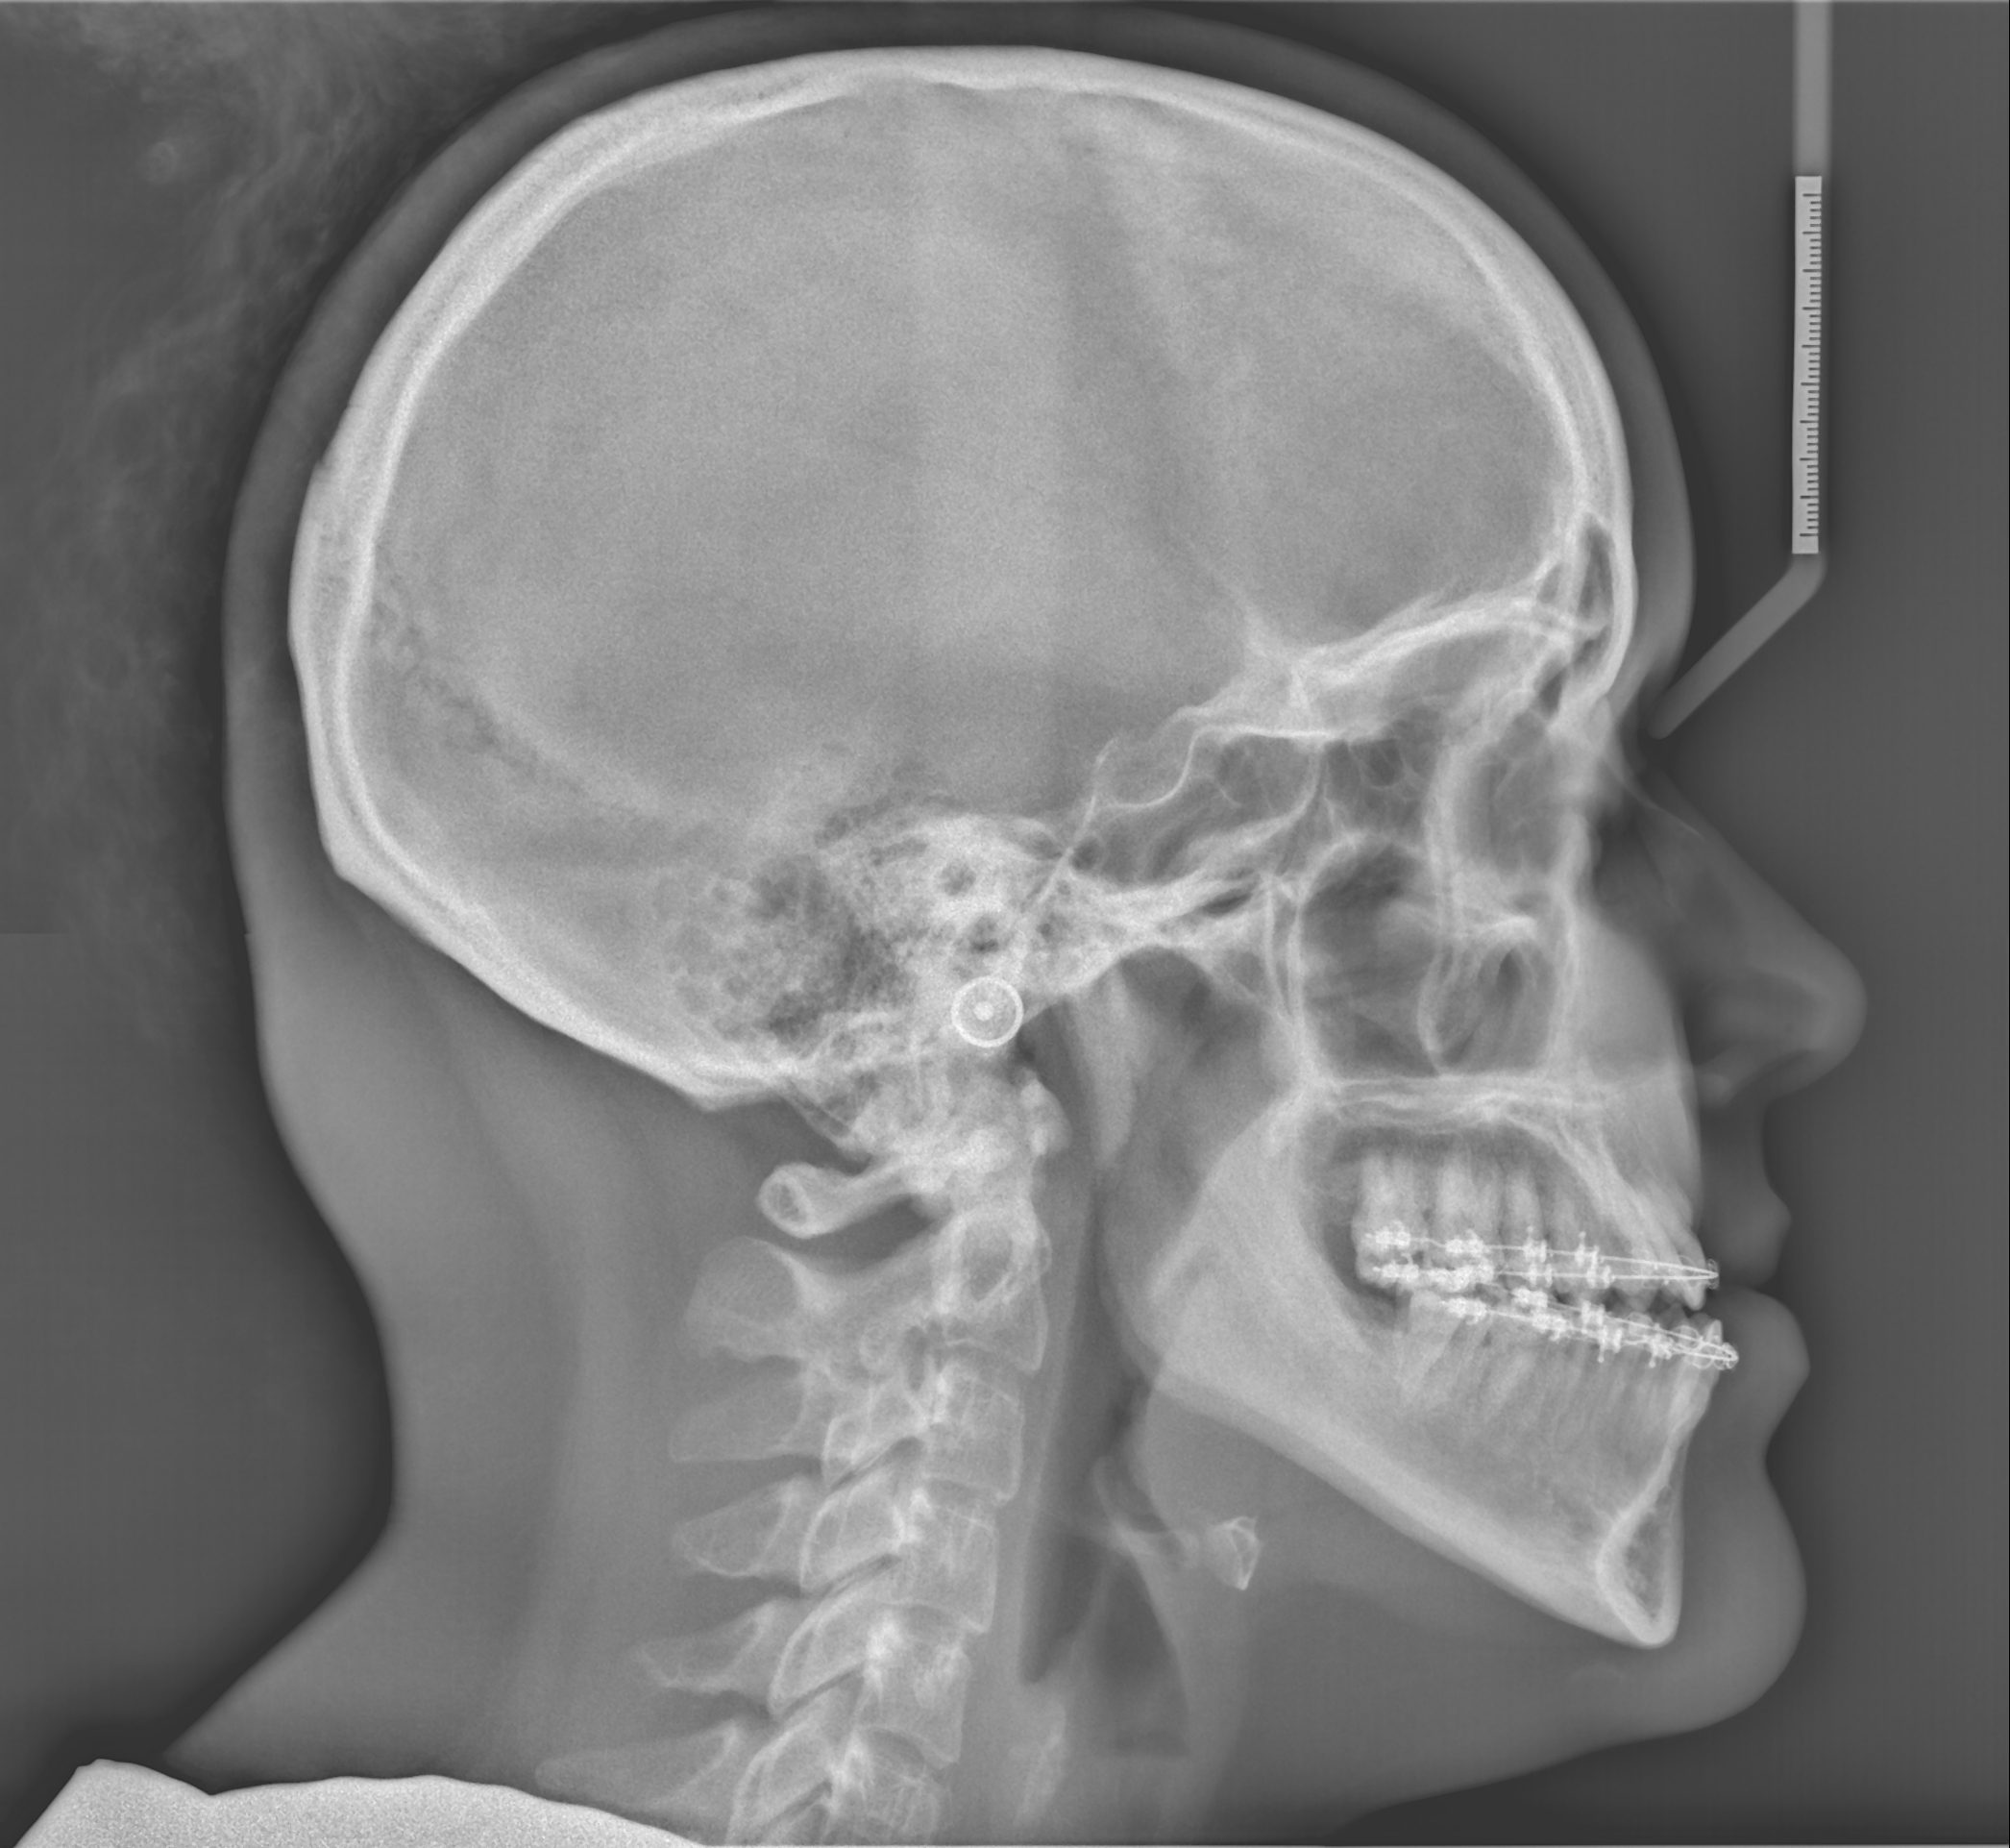

Ce rendez-vous consiste en la prise de mesures, de radiographies, de modèles et de photos. La chirurgie est planifiée et effectuée dans un premier temps en laboratoire et par la suite reproduite à la salle d’opération.

Nous utilisons de façon routinière les plus récentes techniques de planification chirurgicales par ordinateur. À l’aide des radiographies en trois dimensions (3D), un scan complet de votre squelette facial sera effectué.

À l’aide de ce scan et de vos modèles, la planification de votre chirurgie s’effectuera de façon virtuelle. Cette nouvelle technique permet de repositionner vos maxillaires et d’effectuer votre chirurgie orthognatique en trois dimensions de façon plus précise et d’obtenir de meilleurs résultats.

Cette planification chirurgicale par ordinateur est ensuite reproduite lors de votre chirurgie.